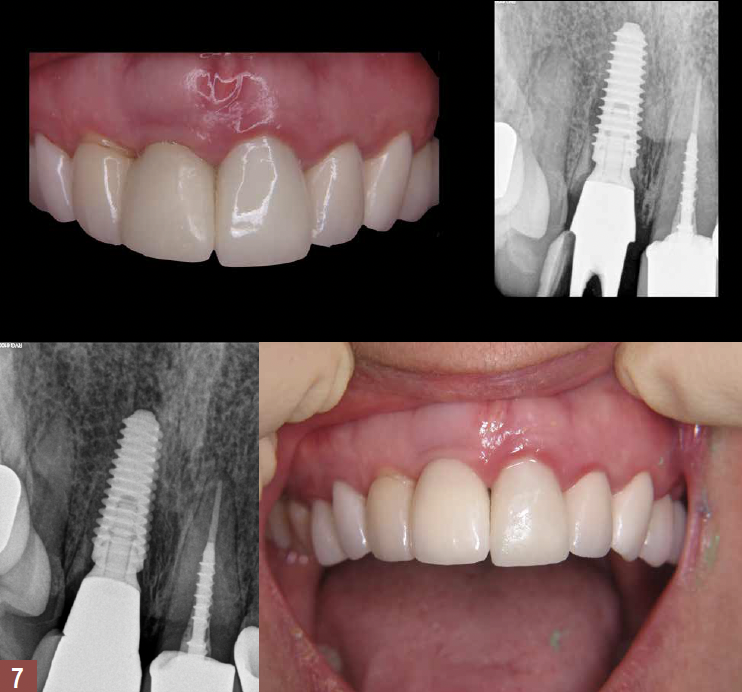

Three months postoperatively, the patient returned for final impressions. Radiographs and ISQ measurement revealed excellent healing, and intraoral inspection showed proper emergence profiling with adequate soft tissue development. A final impression was performed and a final crown was inserted at the 3 month follow-up visit (Figure 7). Long-term 5-year follow-up revealed excellent stability. The use of CBCT and IOS reduced the duration of treatment and the number of office visits for the patient.

Fig 7. Top right panel: Postoperative radiograph at the 3 month

follow-up visit. Prefabricated coping was picked up and sent for

porcelain. Top left panel: Postoperative insertion photograph at the

3 month follow-up visit. Five-year follow-up periapical radiograph

(bottom left panel) and photograph (bottom right panel) reveal

healthy stable hard and soft tissue.